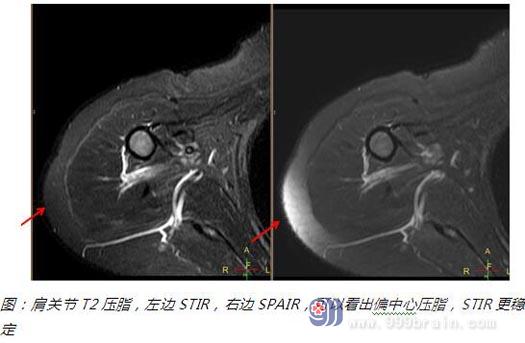

二是不依赖于磁场均匀性,在难压脂部位,大范围压脂部位,偏中心压脂部位STIR都是比较理想的解决方案。

⑤可以用于做偏中心部位的压脂(如肩关节)。